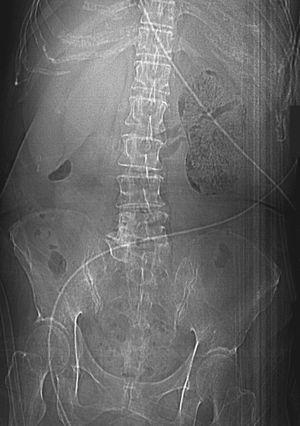

What is the diagnosis? Adrenal carcinoma Autosplenectomy Diverticular abscess Emphysematous pyelonephritis Renal vein thrombosis ( Blood tests showed leukocytosis and hyperglycemia. Urinary microscopy revealed pyuria. Unenhanced computed tomography was performed and revealed extensive gas collection in the parenchyma of the left kidney, the perinephric space, and the left renal vein, with corresponding hydronephrosis and hydroureter. )